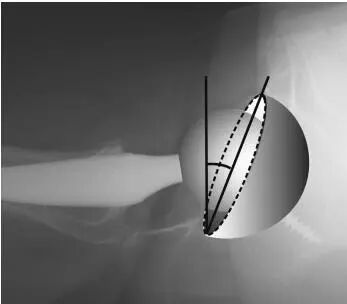

1.Lewinnek’s method:D1是垂直于髋臼假体长轴绘制的椭圆的短轴距离;D2是它的最大直径(图1)(anteversion=arcsin[D1/D2])

3.Liaw’s method:β是臼杯的长轴(从A点到B点的直线)和连接椭圆顶点和长轴端点的线(从A点到C点的线)形成的角度(图3)。

5.Woo and Morrey’s method:这种方法使用cross-table侧位片来测量。这种方法不需要方程,并区分前倾和后倾。该角度是直接测量垂直于工作台的直线和切向臼杯开口面的直线之间的角度。这个角度被定义为从cross-table横向视图的前倾角。